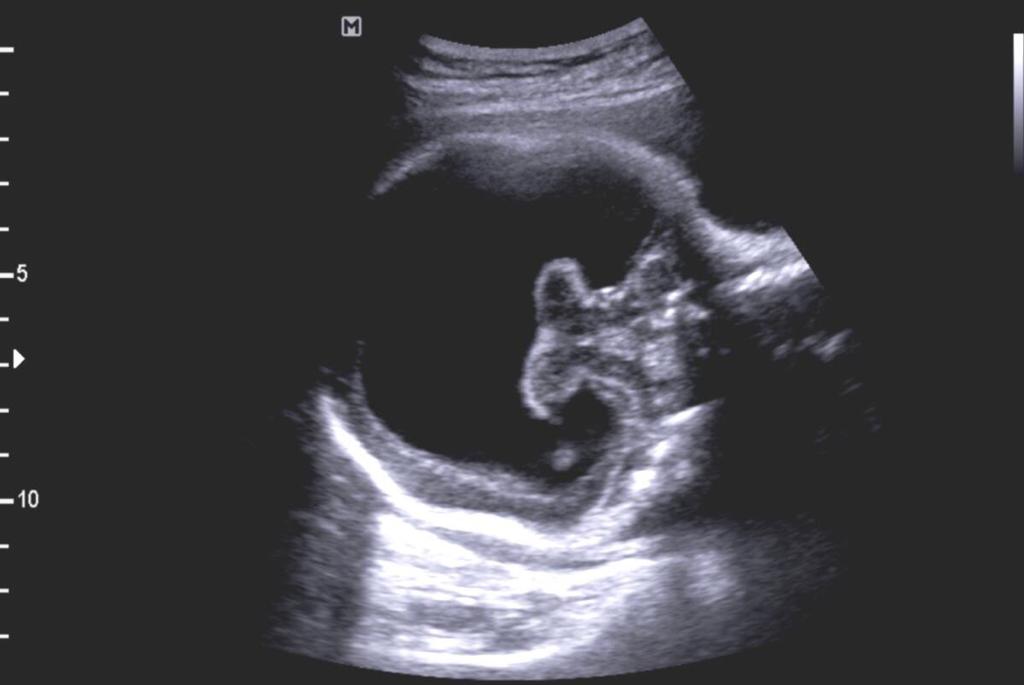

Holoprosencefalia alobar

Se caracteriza por marcados alteraciones en la línea media del encéfalo y/o malformaciones faciales.

- Fusion completa de los hemisferios cerebrales

- Ausencia de la fisura interhemisferica y de la hoz cerebral

- Agenesia del cuerpo calloso y de la comisura anterior

- Holoventriculo, quiste dorsal

- Ausencia de septum pellucidum

- Los ganglios de la base de tálamos pueden estar diferenciados, funcionado o ausentes